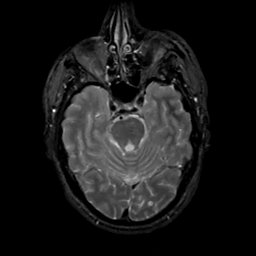

MR Study #15, June 9, 1991 -- Slice #16